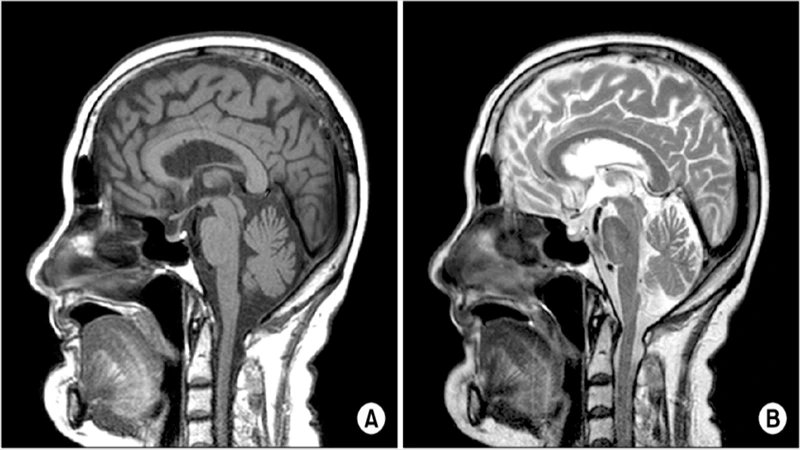

Side-by-side T1 and T2 MRIs of a brain, with labels showing that CSF is dark on T1 and bright on T2.

The T1-weighted sequence is the workhorse for visualizing normal anatomy. It provides excellent contrast between different soft tissues, making it easy to distinguish gray matter from white matter in the brain, for example.

• Key Characteristic: Fat is bright, and water (like cerebrospinal fluid, or CSF) is dark.

The T2-weighted sequence is extremely sensitive to changes in water content. Since most pathologies—such as tumors, inflammation, infection, and trauma—involve an increase in water (edema), they will appear bright on a T2 image.

• Key Characteristic: Water and fat are both bright.